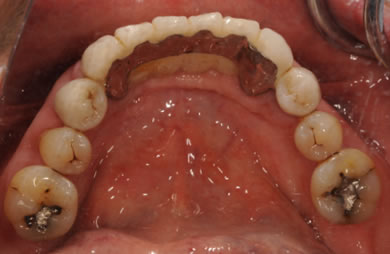

インプラントの症例写真 IMPLANT

骨再生スピードインプラント治療+AGC連結セラミック治療+セラミック治療

| 主訴 | 歯周病の治療およびインプラント治療や義歯治療について相談したい。 | ||||||||||||||||||||||||||||||||

| 治療方針 | ソケットリフト法により上顎洞底部を拳上することにより、骨の無い部分に骨をつくってあげ、インプラント治療を可能にする。さらに歯周病により組織の破壊が著しいので、AGC連結セラミック治療により上顎の審美的回復を行う。 | ||||||||||||||||||||||||||||||||

| 治療内容 | インプラント7本(抜歯AGC即日スピードインプラント+ソケットリフト)、AGCハイブリッドセラミック連結ブリッジ1装置(上顎)ハイブリッドセラミック8本 | ||||||||||||||||||||||||||||||||